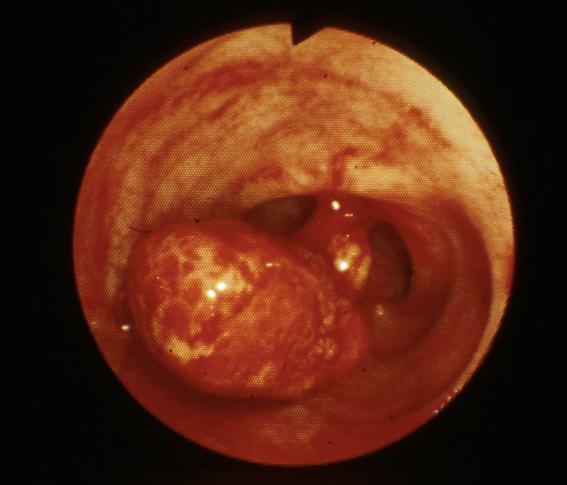

疾病(病理主体)的分类肿瘤样病变/幼年性息肉

部位(按器官分)大肠/乙状结肠

检查方法内窥镜

肿瘤的肉眼分类0型(表在型)/I型(Ip)

肿瘤最大直径25~29